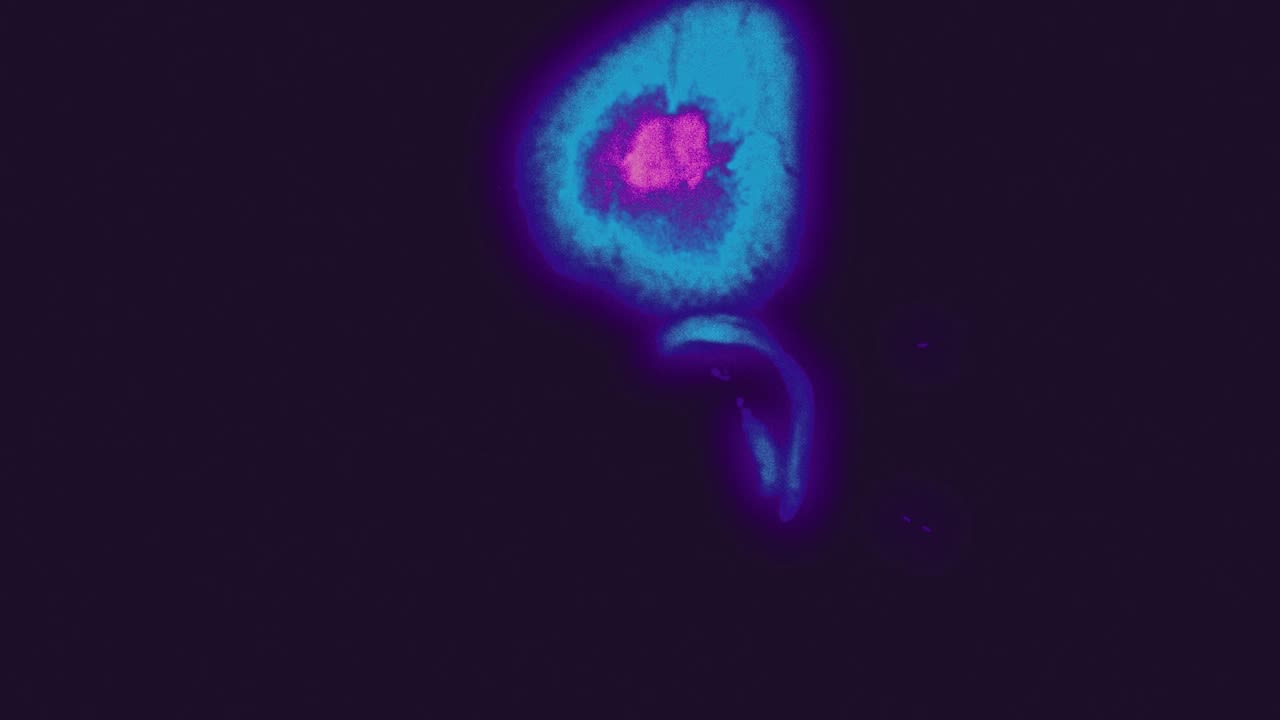

MRS uses the same scanning machine as MRI. While MRI creates map-like images of a tumour, MRS generates its “molecular fingerprint”.

The output is a complicated graph that researchers can analyse to understand the amounts of different chemicals inside cancer cells.

With support from Cancer Research UK and others, the team showed that MRS can capture impressive detail about medulloblastoma – in real-time, without sending a physical sample for lab-based analysis.

“The molecular fingerprints of the four medulloblastoma groups look very different,” says Peet.